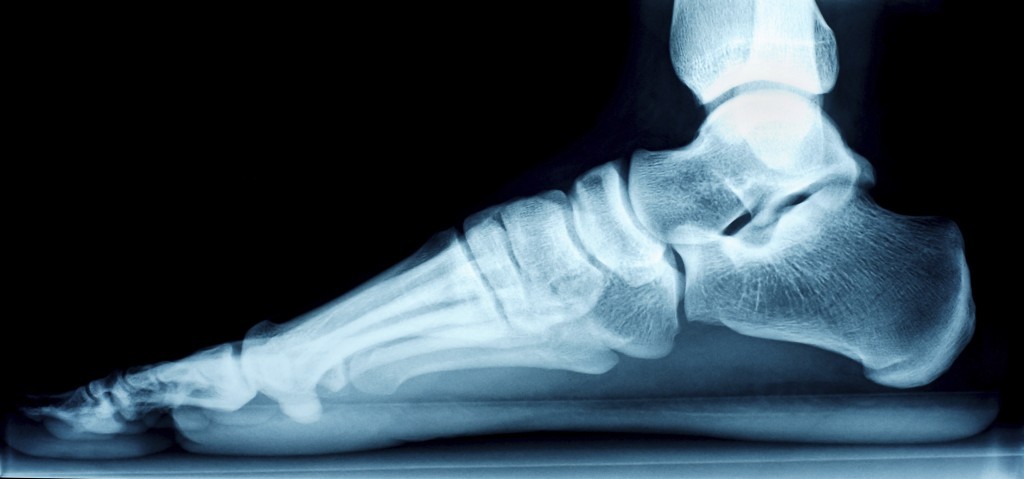

radiografia

È possibile intervenire per creare o migliorare l’arco plantare, effettuando specifici esecizi fisici.

Gli specialisti propongono esercizi di ginnastica correttiva secondo le tecniche I.D., cioè con le specifiche approvate dall’Istituto Duchenne, che vanno studiate in modo specifico per ogni caso e, solo dopo aver preso l’impronta del piede del bambino, per identificare univocamente la tipologia del difetto plantare.